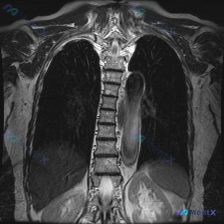

一开始提的是“Scoliosis(脊柱侧弯)”,但看胸部MRI T2加权冠状位影像,重点反而不在侧弯本身——

- 左侧胸腔后部、脊柱旁沟有个巨大长椭圆形占位,长轴垂直,边缘光滑包膜完整

- 内部T2信号不均匀,有层状分区,包膜低信号

- 占位效应明显:左肺受压含气减少,纵隔轻度右推,心影大血管位置受影响

- 临近胸椎肋骨骨质信号没看到明确破坏,胸膜也没明显增厚结节

- 看起来上缘约T3-4,下缘似乎到膈下,有跨膈分布的趋势

📋答案:基于现有影像特征(后纵隔/脊柱旁沟、边界清晰光滑包膜完整、T2信号不均、无明显骨质破坏、伴继发性脊柱侧弯),综合概率最高的诊断为:神经源性肿瘤(神经鞘瘤或神经纤维瘤),需重点排除哑铃型肿瘤及恶性周围神经鞘瘤(MPNST)。